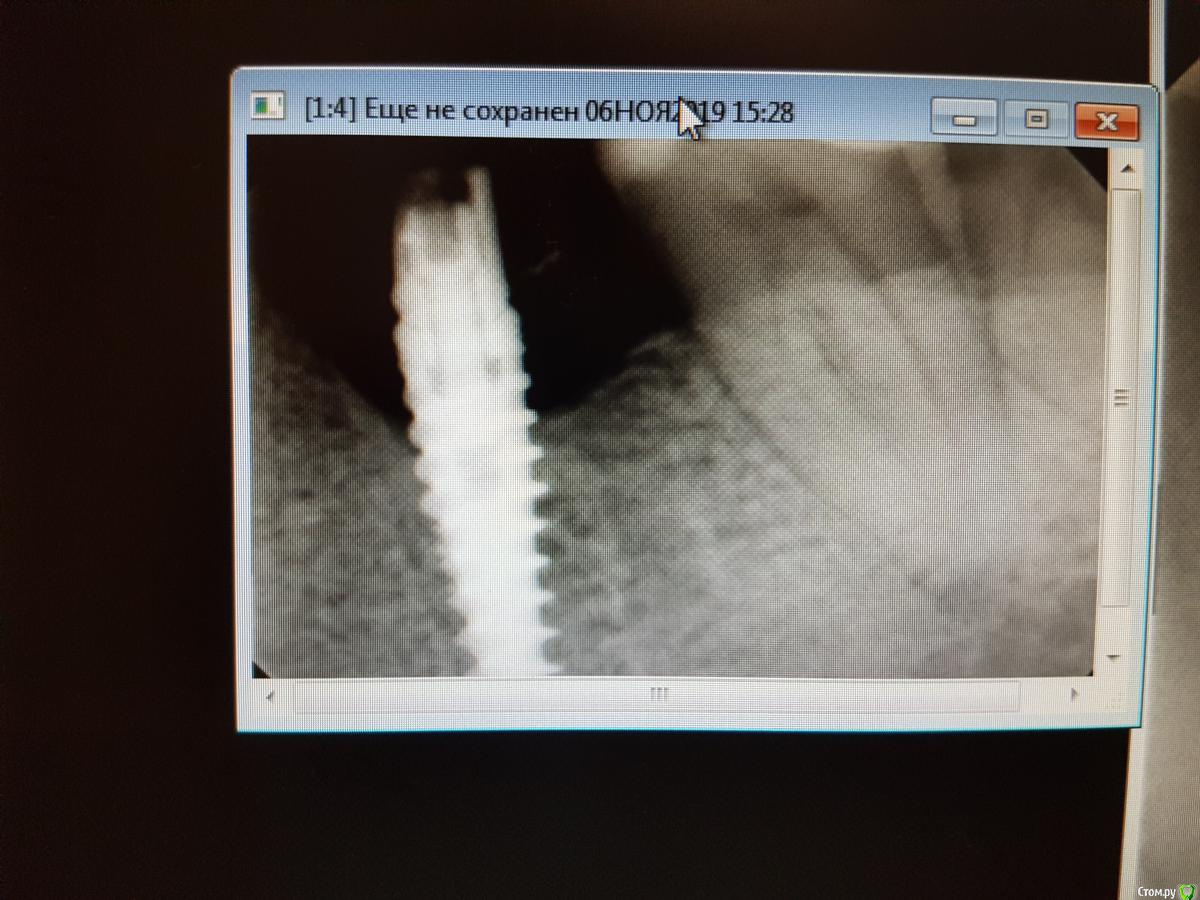

Руслан Аминов Опубликовано 6 ноября, 2019 Поделиться Опубликовано 6 ноября, 2019 Имплант Adin в области зуба 36, установлен в 2015 году. Шахта имплантата выходит язычно. Установлена коронка м/к на абатменте. Коронка расфиксировалась месяц назад, в клинику пациент не обращался. Сейчас десна гиперемирована, отечна, кровоточит при зондировании, при пальпации гноетечение. На Rg кость резорбировалась до 3 витка. На приеме почистили, помыли хг, коронку обработали и зафиксировали на временный цемент. Через неделю ситуация не улучшилась. Подскажите как снять воспаление. Имеет ли смысл проводить мягкотканную пластику? или удаление импланта? Ссылка на комментарий